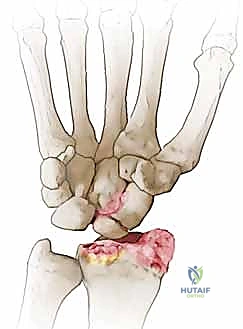

متلازمة SNAC (Scaphoid Nonunion Advanced Collapse) هي حالة تدهور تدريجي ومأساوي لمفصل الرسغ. تبدأ القصة بكسر في العظم الزورقي (غالباً بسبب السقوط على يد ممدودة). إذا لم يتم تشخيص هذا الكسر أو لم يلتئم بشكل صحيح، فإن العظم الزورقي ينقسم إلى قطعتين تتحركان بشكل غير طبيعي ومستقل عن بعضهما البعض.

هذه الحركة غير الطبيعية تخلق احتكاكاً مستمراً (Micro-trauma) مع العظام المجاورة، وتحديداً عظم الكعبرة (Radius). بمرور الوقت (أشهر أو سنوات)، يؤدي هذا الاحتكاك إلى تآكل الغضاريف الناعمة التي تغطي العظام، مما يسبب خشونة مفصلية شديدة (Osteoarthritis).

- المرحلة الثانية (Stage II): يمتد التآكل والخشونة ليشمل المفصل الزورقي الكبير (Scaphocapitate joint).

تُعد عملية استئصال القطب البعيد للعظم الزورقي (Excision of the Distal Pole of the Scaphoid) حلاً جراحياً ذكياً ومبتكراً. الفكرة الميكانيكية وراء هذه الجراحة هي: "إذا كان القطب البعيد للعظم الزورقي هو الذي يحتك بعظم الكعبرة ويسبب الألم والخشونة، فلنقم بإزالته مع الحفاظ على باقي هياكل الرسغ".

- الاستئصال الدقيق: باستخدام أدوات جراحية ميكروسكوبية دقيقة، يتم استئصال حوالي 3 إلى 4 مليمترات من القطب البعيد للعظم الزورقي. هذه الكمية كافية لمنع الاحتكاك مع عظم الكعبرة، وفي نفس الوقت تحافظ على استقرار الأربطة.